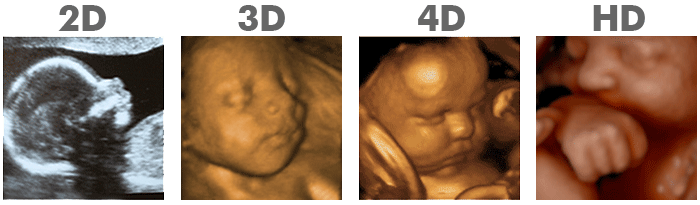

Standard or 2D ultrasound.

3D ultrasound. Create a real picture of the baby.

4D ultrasound. Like 3D ultrasound, it creates a real image, but with movement.